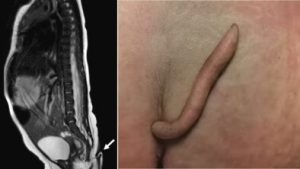

في واحدة من الحالات النادرة ولدت طفلة عن طريق عملية قيصرية لأبوين أصحاء فى العشرينيات من العمر، اكتشف الأطباء بسرعة ذيلًا يبلغ طوله 5.7 سم مغطى بالجلد والشعر الناعم.

وقال الأطباء، إن الذيل كان ناعمًا ومغطى بالجلد والشعر الناعم ويمكن تحريكه دون أى ألم لكنه لم يظهر أى حركة تلقائية، وقد بكت الطفلة عندما قرصت بإبرة على الهيكل.

وكشفت عمليات المسح، أن الذيل لم يكن نتيجة لمشكلة فى العمود الفقرى، وهى حالة يمكن أن تتسبب فى ظهور نمو يشبه الذيل فى أسفل العمود الفقرى، وخرجت الطفلة من المستشفى فى نفس اليوم ولم تعان من أى مضاعفات.

وكشف التحليل الإضافى للذيل، أنه يحتوى على أنسجة رخوة وشرايين وأوردة وحزم أعصاب، ولاحظ الفريق الطبى أن “ذيول الإنسان الحقيقية” نادرة للغاية حيث تم تحديد 195 حالة فقط بحلول عام 2017 وأطولها 20 سم (7.9 بوصة).